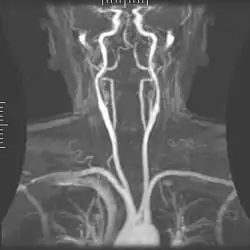

Angiography

Magnetic resonance angiography

Magnetic resonance angiography (MRA) generates pictures of the arteries to evaluate them for stenosis (abnormal narrowing) or aneurysms (vessel wall dilatations, at risk of rupture). MRA is often used to evaluate the arteries of the neck and brain, the thoracic and abdominal aorta, the renal arteries, and the legs (called a "run-off"). A variety of techniques can be used to generate the pictures, such as administration of a paramagnetic contrast agent (gadolinium) or using a technique known as "flow-related enhancement" (e.g., 2D and 3D time-of-flight sequences), where most of the signal on an image is due to blood that recently moved into that plane (see also FLASH MRI).[53]

Techniques involving phase accumulation (known as phase contrast angiography) can also be used to generate flow velocity maps easily and accurately. Magnetic resonance venography (MRV) is a similar procedure that is used to image veins. In this method, the tissue is now excited inferiorly, while the signal is gathered in the plane immediately superior to the excitation plane—thus imaging the venous blood that recently moved from the excited plane.[54]